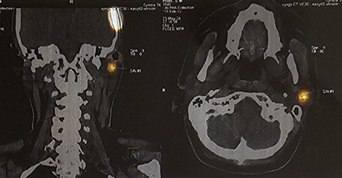

У 2024 році було виявлено 174 пацієнти з меланомою, з яких 120 — на І–ІІ стадіях захворювання, а 34 — на занедбаних ІІІ–IV стадіях. Спеціалізоване лікування отримали 92,5% пацієнтів, що становить 161 особу.

За 9 місяців 2025 року зареєстровано 140 нових випадків меланоми: 100 пацієнтів — на І–ІІ стадіях та 24 — на ІІІ–IV стадіях. Спеціалізоване лікування отримали 92% пацієнтів (129 осіб).

Станом на вересень 2025 року на обліку у Львівській області перебуває 2249 пацієнтів із меланомою, з яких 1483 особи знаходяться під наглядом понад 5 років.